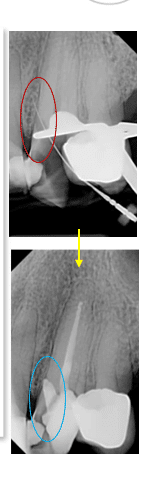

- Confirm with a periapical radiograph to identify the location, size and depth of perforation.

Step 1: start quickly

Step 2 and Step 3

Step 2: clean the perforation site

Step 3: control bleeding

Step 4 and Step 5

Step 4: Prepare MTA

Step 5: put MTA into the perforation

Step 6: Provide Moisture for Setting

Important sequence

Apply MTA, cover it with a temporary restoration, wait for proper setting, then complete the definitive coronal restoration.